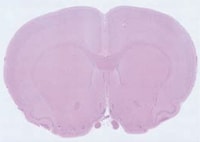

透射的照明通常用于两种不同类型的样本:透明或半透明的物体或不透明的物体,并且需要背光进行测量。对于这种类型的设置,光线从物体后面闪耀,通过它,并由眼睛或相机接收。这种照明主要用于生物应用,其中用户是玻璃载玻片或其他标本夹持器上的成像细胞或组织。在背光一个对象时,它还适用于创建其配置文件明确的轮廓,允许更精确和准确的测量。

当在低放大率下观察样品时,光均匀地施加到整个目标。随着放大率的增加,可以集中光以改善图像的对比度。

(200×,120张综合)